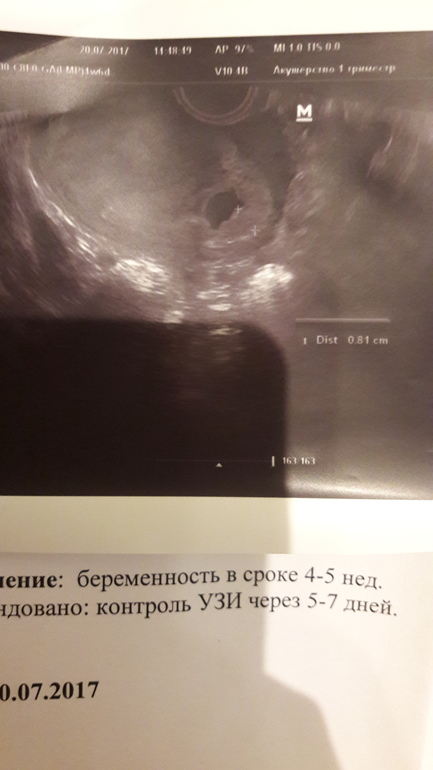

Свд узи

Свд узи 116 фото